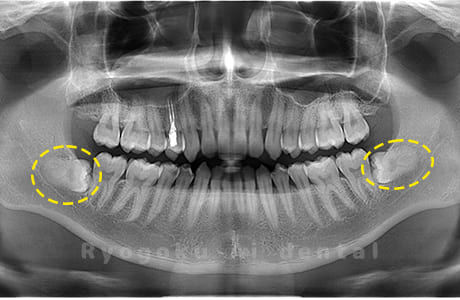

Case01

- 原因

- 水平埋伏智歯

- 治療内容

- 下顎の水平埋伏智歯を抜歯

<リスク・副作用>

手術後は痛み、腫れ、痺れなどの副作用が生じる場合があります。